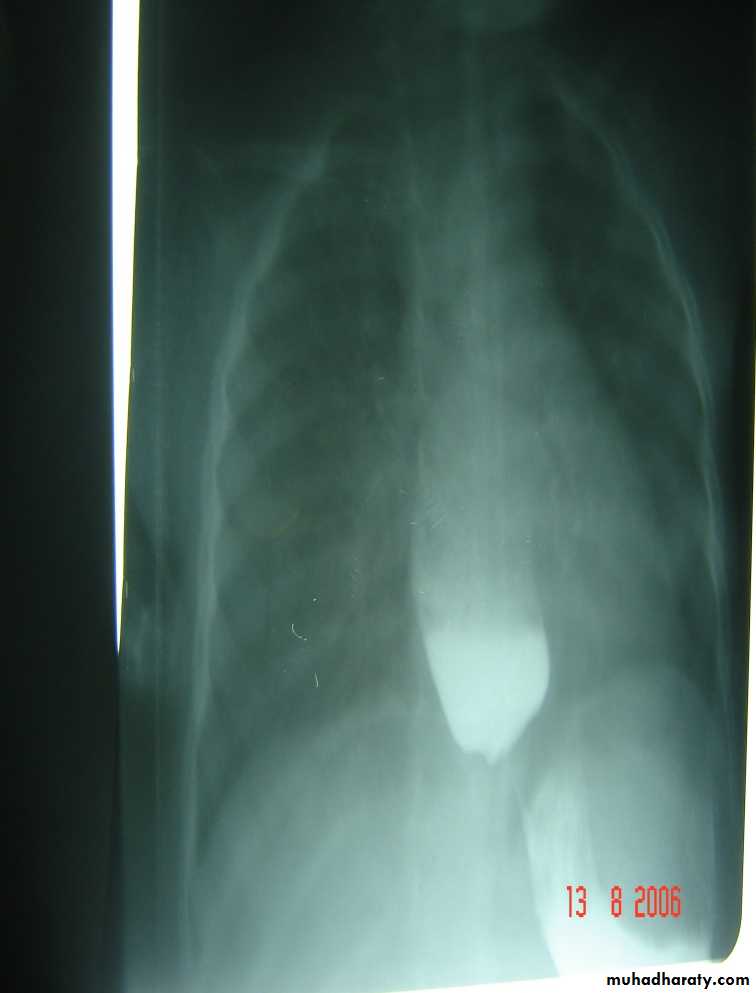

Oesophageal Atresia and Tracheo-Oesophageal Fistula,